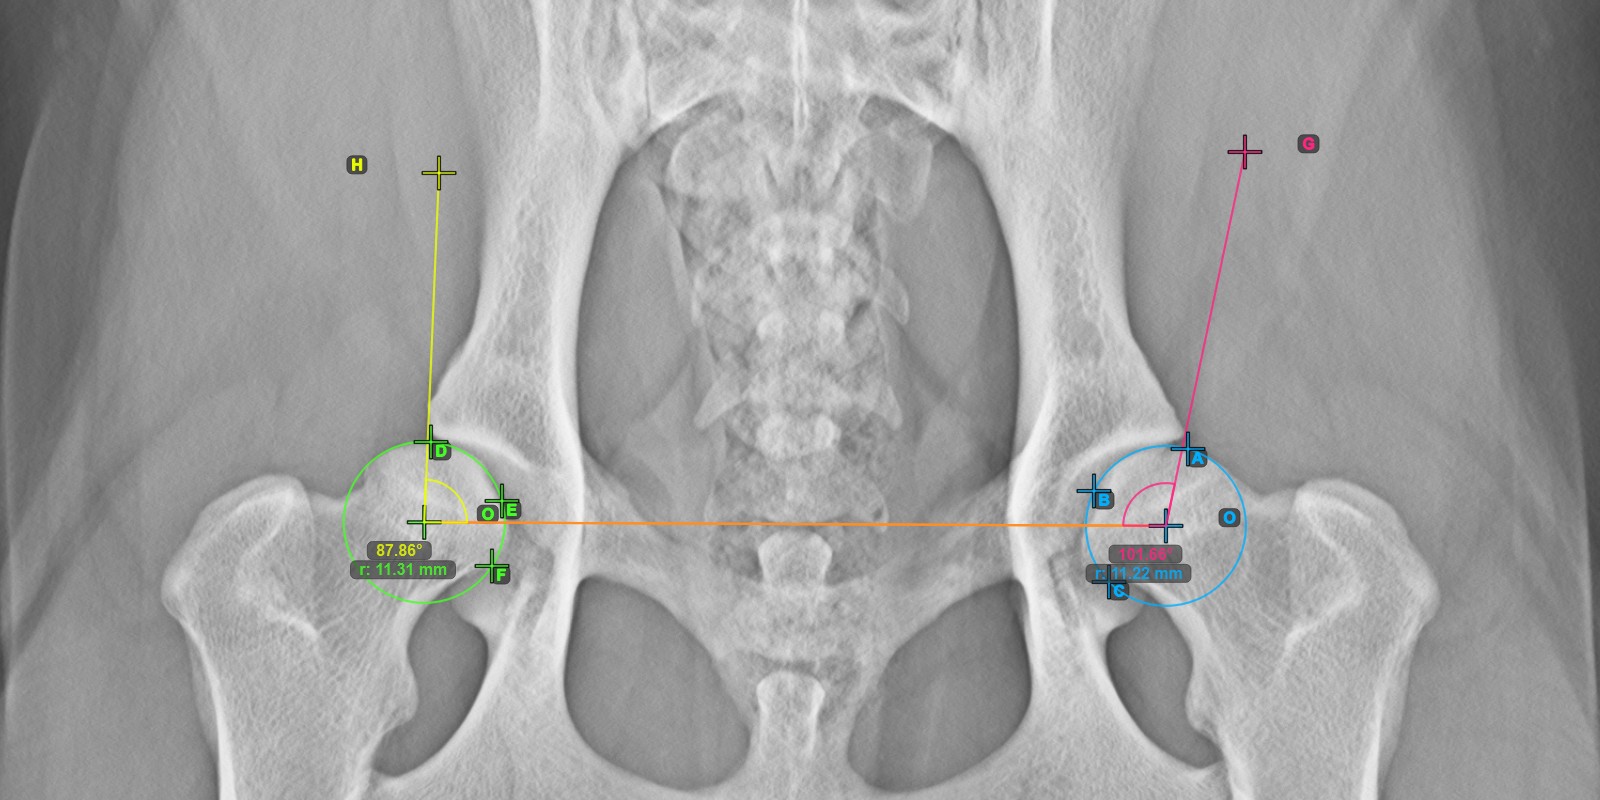

Berechnen Sie den rechten Norberg-Winkel, indem Sie eine Linie an der effektiven Kante des rechten Acetabulumknochens markieren und damit die gesamte erweiterte Messung abschließen.

Setzen Sie einen Punkt in der Nähe des rechten Caput Femoris und ziehen Sie ihn entlang der effektiven Kante des rechten Acetabulumknochens, um die Schenkelseite des rechten Norberg-Winkels zu bilden.

Die gezeichnete Linie muss eine Tangente an der effektiven Kante des rechten Acetabulumknochens sein. Der Wert und der Bogen des Winkels werden automatisch berechnet.

Das Bild unten zeigt die typische Platzierung der Linie und die berechnete Norberg-Winkel-Messung.

../../_images/image71.jpg